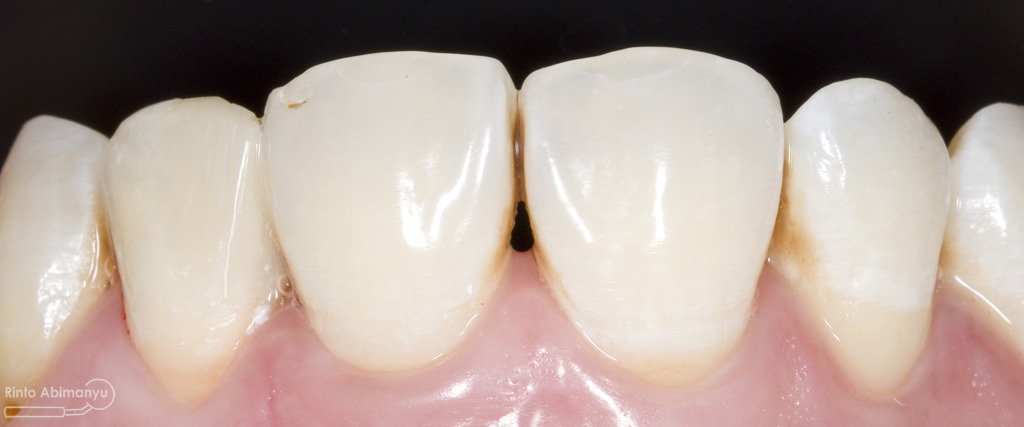

Pada pemeriksaan intra oral terlihat gigi 23 dan 24 mengalami karies dan cukup banyak sisa makanan terjebak disana…

Pemeriksaan respon dingin pun menunjukkan hasil negatif, untuk menambah data dalam penegakan diagnosis maka dilakukan pengambilan ronsen pada gigi2 tersebut